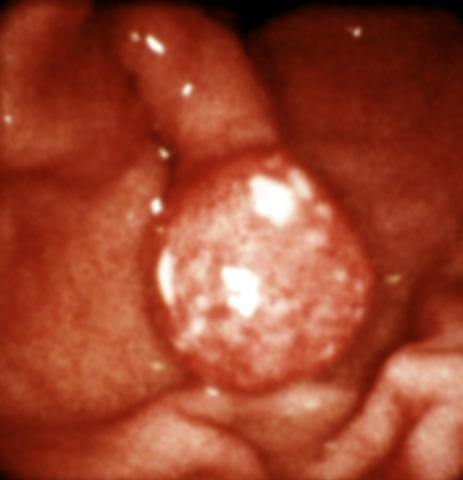

Рис. 11. Эндоскопическая картина желудка в норме и при различных заболеваниях. Полип желудка на ножке.